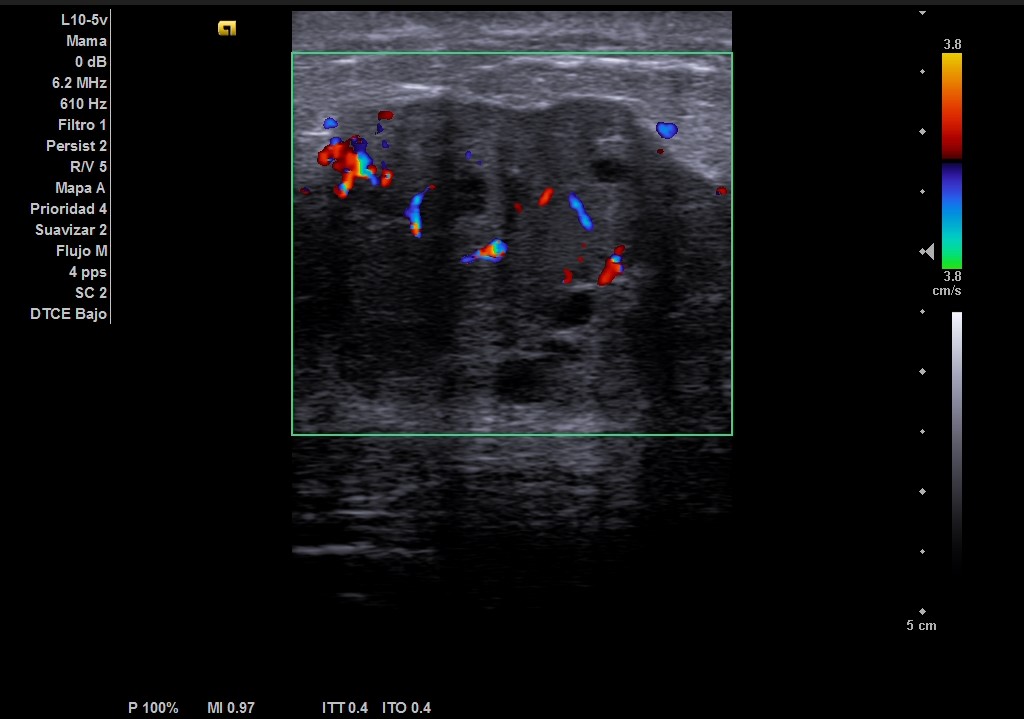

Ecografía: mama izquierda se observa tumoración hipoecogénica lobulada en cuadrante superior externo de aproximadamente 4 cm, heterogénea, que capta al Doppler color y dos adenopatías de aspecto reactivo en axila homolateral. Imagen sospechosa de malignidad.